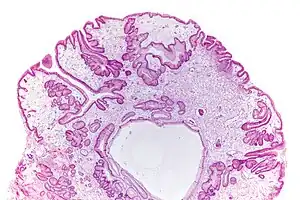

Micrograph of a gastric juvenile polyp, as may be seen in juvenile polyposis syndrome. H&E stain

Juvenile polyposis syndrome is an autosomal dominant genetic condition characterized by the appearance of multiple juvenile polyps in the gastrointestinal tract. Polyps are abnormal growths arising from a mucous membrane. These usually begin appearing before age 20, but the term juvenile refers to the type of polyp (i.e benign hamartoma, as opposed to adenoma for example), not to the age of the affected person.[1] While the majority of the polyps found in juvenile polyposis syndrome are non-neoplastic, hamartomatous, self-limiting and benign, there is an increased risk of adenocarcinoma.